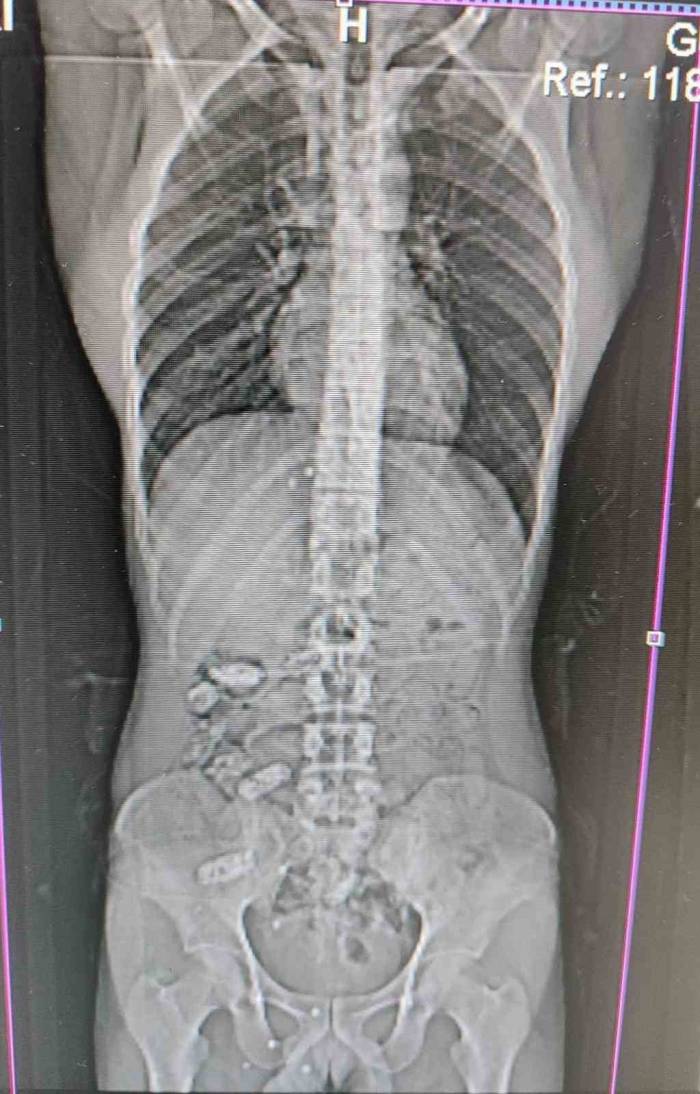

Edinilen bilgilere göre, Gümüşhane İl Emniyet Müdürlüğü'ne bağlı Narkotik Suçlarla Mücadele Şube Müdürlüğü ekipleri tarafından Akçakale Uygulama Noktası'nda durdurulan bir araç içerisindeki yabancı şahsın şüpheli hareketleri üzerine çalışma yapıldı. Uyuşturucu kuryesi olduğu ve yutma suretiyle uyuşturucu taşıdığından şüphelenilen şahsın Gümüşhane Devlet Hastanesi'nde yapılan kontrollerinde, midesinde 18 adet kapsül olduğu tespit edildi. Hastanede yapılan müdahalenin ardından şahsın midesinden çıkarılan kapsüllerin içerisinde toplamda 152,29 gram metamfetamin ele geçirildi.